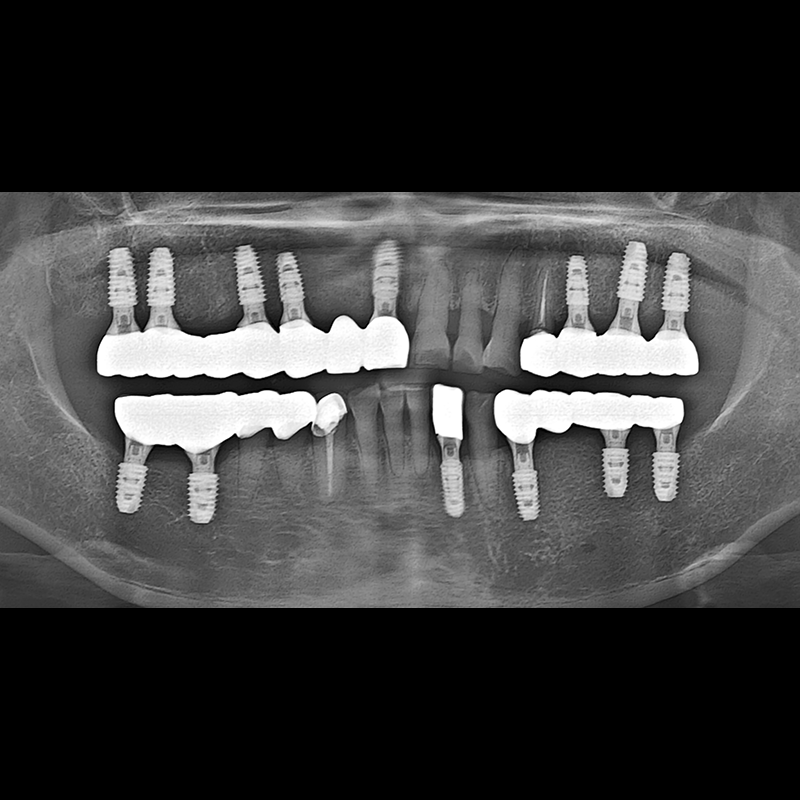

BEFORE AFTER

Implant before and after 2025.05.30

Implants were placed in the missing tooth and in the tooth position where it was difficult to save.